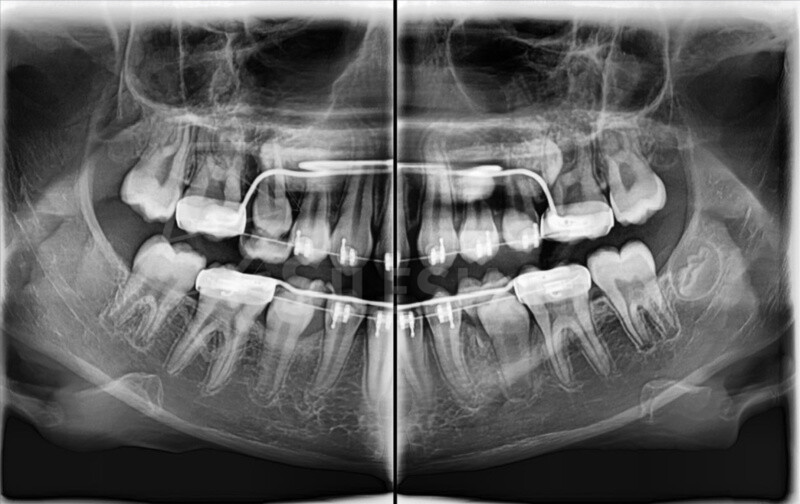

Pracownia wyposażona jest w tomograf stożkowy Vatech Green X (model 2025) – najnowszej generacji urządzenie, które łączy najwyższą jakość obrazów 2D i 3D z minimalną dawką promieniowania.

CBCT (tomografia stożkowa) to nowoczesne badanie 3D, które pokazuje zęby, kości, zatoki i stawy skroniowo-żuchwowe w pełnym trójwymiarze. Umożliwia bardzo dokładne zaplanowanie leczenia chirurgicznego, ortodontycznego, implantologicznego i laryngologicznego.

• Najnowocześniejszy tomograf stożkowy w regionie – Vatech Green X (model 2025).